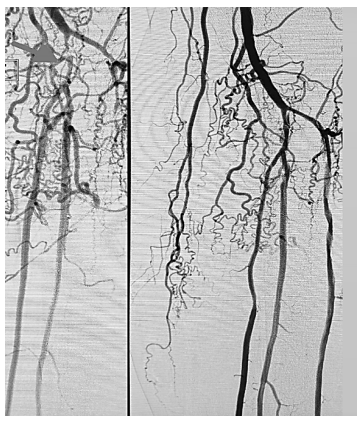

Observe a imagem a seguir.

A imagem acima corresponde a uma angiografia digital demonstrando o pré e pós procedimento de angioplastia de membro inferior esquerdo. Qual é a estrutura anatômica assinalada em seta?